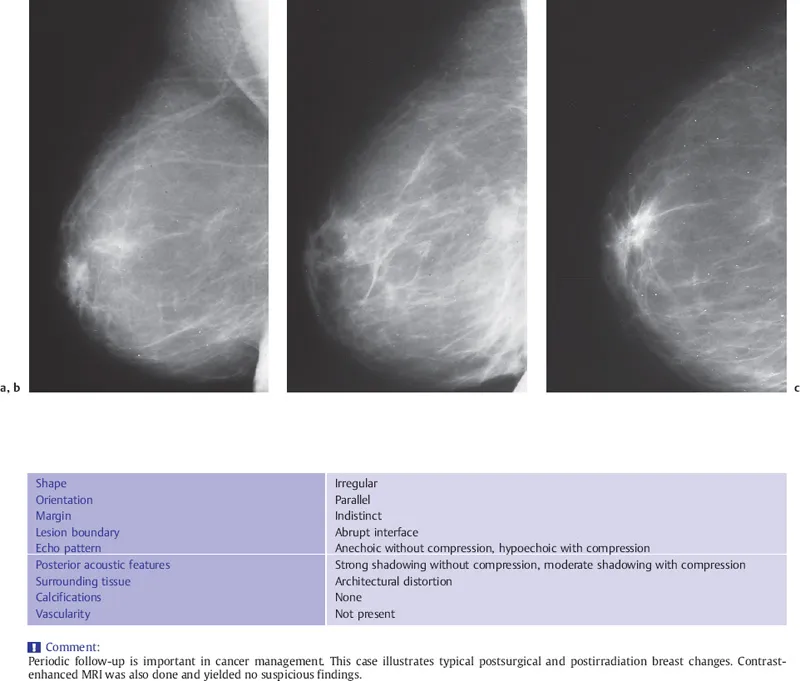

Surgical Sequelae - Surgical Souvenirs

- Common Post-Op Changes (All Modalities):

- Early: Seroma (clear fluid), hematoma (blood), edema, skin thickening. Usually resolve.

- Late: Scar/fibrosis (spiculated, stable/shrinking), fat necrosis (oil cysts: lucent mammo, anechoic US; dystrophic calcifications: coarse, rim), architectural distortion.

- Surgical clips: Mark lumpectomy bed.

- Lumpectomy Cavity: Evolves from fluid → granulation tissue → scar. Stability is key.

⭐ > A post-surgical scar can mimic malignancy (spiculation) but stability or regression on serial imaging is reassuring; growth is a red flag.

Radiation & Systemic Rx - Ray & Rx Remnants

- Radiation Therapy (RT) Changes:

- Acute (0-6 months): Skin thickening, ↑ breast density, edema, ill-defined haziness.

- Developing (6-12 months): Peak skin changes, early fibrosis, architectural distortion may begin.

- Chronic (>12 months): Established fibrosis, scarring, architectural distortion, fat necrosis (oil cysts, dystrophic calcifications), skin retraction, telangiectasias, volume ↓.

Differentiating Benign Changes:

- Scar: Stable/retracts over time. Initial distortion possible.

- Fat Necrosis: Oil cysts, dystrophic Ca++ (rim/coarse). Predictable evolution.

- Seroma: Simple fluid, resolves/shrinks.